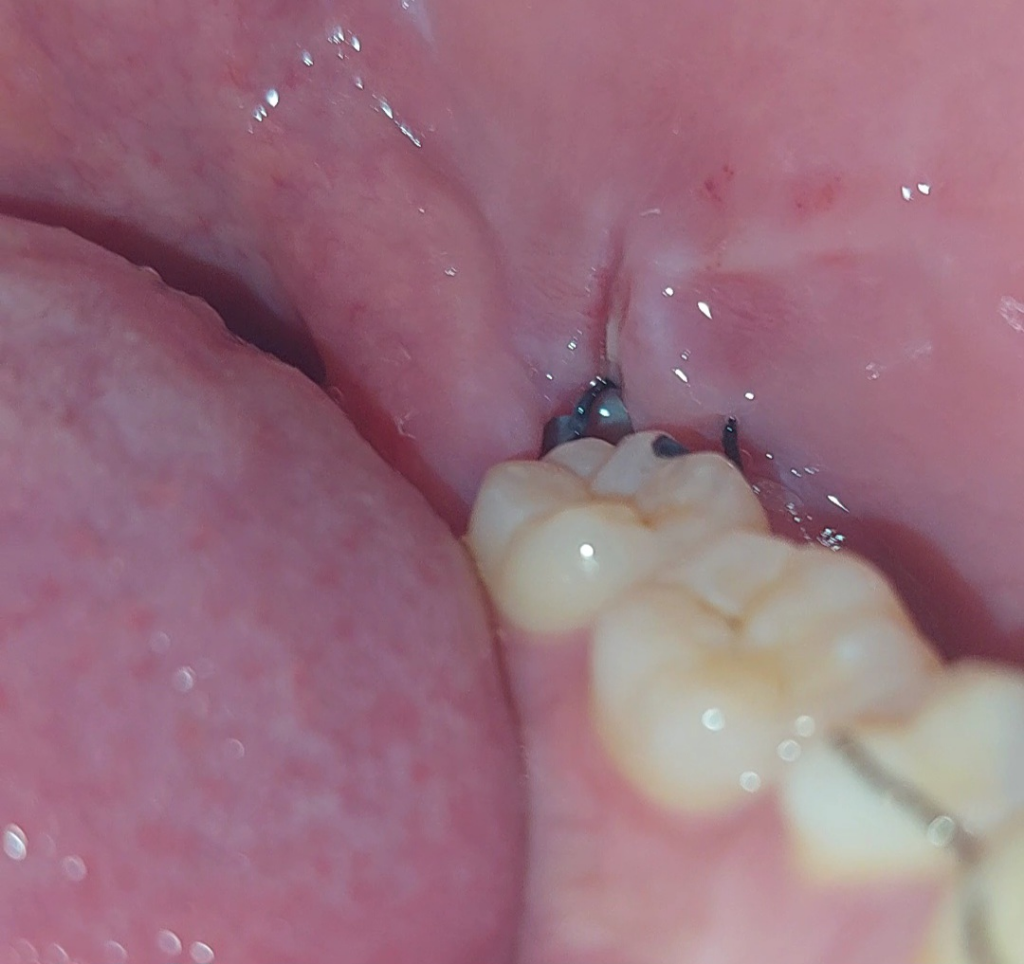

사랑니 발치부위에 웬 빵꾸가났어요. 깊이도 꽤 깊어요.

아래쪽 사랑니를 발치하고 5일차입니다

지금보니까 깊이도 꽤 깊고 안쪽은 회색을띄고있습니다.

채워진 혈병이 떨어져서 저렇게 된걸까요..?

• 2번 째 사진